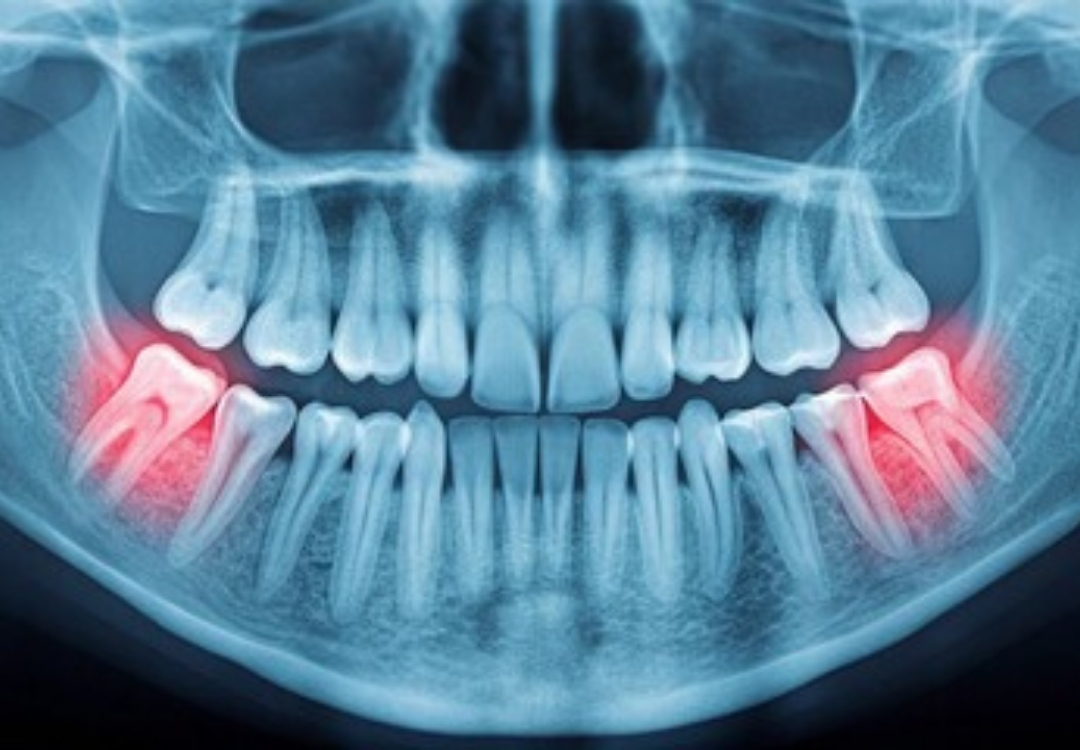

岩出市清水の歯医者「はたなか歯科クリニック」では、レントゲン検査などで親知らずの位置や向きを確認し、お口の状態に合わせた適切な対応と口腔外科を行っています。

痛みがある場合だけでなく、将来的なトラブルを防ぐためにも、早めのチェックをおすすめします。